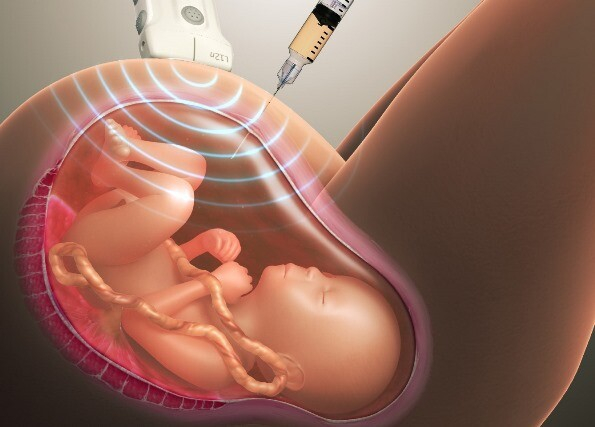

— Для того чтобы прояснить ситуацию, разумеется, необходима ДНК-экспертиза. Во время беременности получить материал с ДНК ребенка можно с помощью инвазивных манипуляций (биопсии ворсин хориона, амниоцентеза — пункции амниотической полости с целью получения материала для последующего лабораторного исследования).

Существуют и неинвазивные исследования (во время которых на организм не оказывается никакого воздействия с помощью игл или различных хирургических инструментов). Однако они недостаточно достоверны.